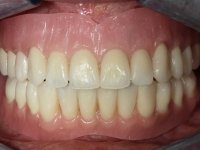

The overdentures with a metallic framework were fabricated over the bars, according to the silicone walls previously made. Before finishing the dentures, a new functional and aesthetic evaluation of the teeth was done, together with a new jet-bite registration to allow small occlusal adjustments.

The bars were finally screwed over the implants with the adequate torque and the overdentures set-in-place. Maintenance instructions were given to the patient regarding oral hygiene and overdentures insertion / removal.